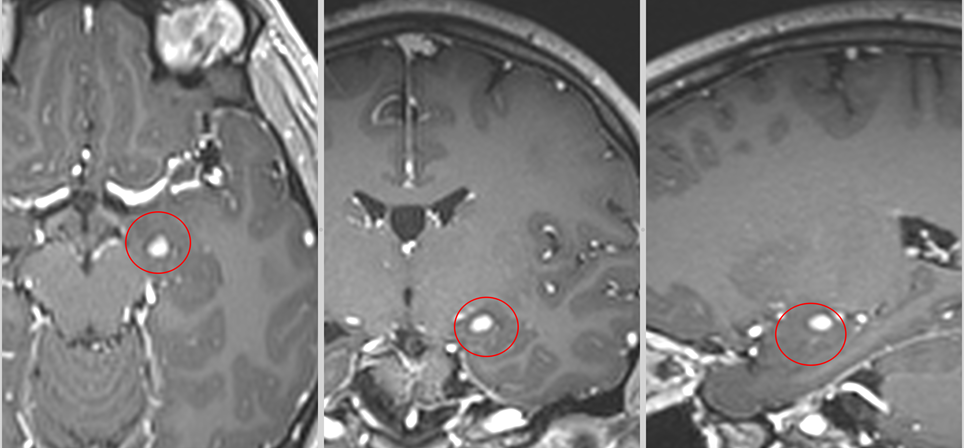

Primele imagini RMN realizate imediat după intervenție au confirmat absența complicațiilor. Câteva săptămâni mai târziu, un nou control imagistic a arătat clar rezultatul: tumora fusese îndepărtată în totalitate.

Investigațiile următoare, întâi peste 3 luni apoi peste încă un an au confirmat: nici o urmă de rest sau recidivă tumorală.

La aproape 3 ani de la operație, fără crize epileptice, fără deficite neurologice și cu un RMN curat putem considera că pacienta este vindecată.